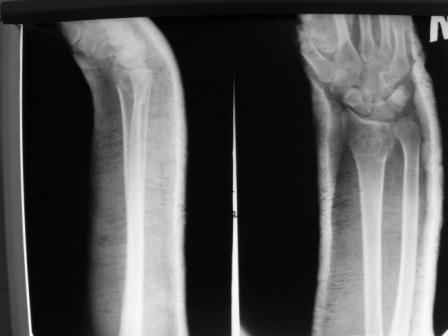

Уважаемые коллеги.Прошу обсудить случай лечения перелома дистального метаэпифиза лучевой кости. Ситуация скандальная и крайне неблагоприятная. Больная с патологической обстоятельностью мышления, склонностью к сутяжничеству, патологическими умозаключениями, не поддающимися коррекции (см. психиатрию, правда офиц. диагноза нет). В данном случае есть ряд ошибок с нашей стороны, прежде всего в отношении качества ведения документации (за что получил административное взыскание, по делом мне дураку). В остальном- придерживались в лечении подхода классический советской школы. Так как умную операцию…… сами знаете… 15.12- перелом луча в Москве. Там же репозиция, гипс. Дальнейшее лечение у нас в ЦРБ. 20.12.- вторичное смещение в гипсе21.12- под внутривенным наркозом- репозиция, гипсовая лонгета. Дальше начинается самое интересное. После репозиции больная заявила, что я (репозицию делал я) порвал ей все связки в суставе, посинел у нее 5 палец, якобы я за него тянул и т. д. На самом деле на 2 сутки после репозиции рука немного отекла и было незначительное сдавление гипсом, который был ослаблен. Дальнейшее лечение консервативное. Через 6 недель- гипс снят, назначено ЛФК. Пациентка крайне недовольна. Говорит, что на снимке у нее выступает кость, я ей сломал руку и.т.д. В общем началось. Пациентка прочитала в интернете наверное все, что есть по данной травме.По заключениями рентгенологов и консультанта из КДЦ областной больницы - стояние отломков допустимое. Объективно говоря- снижена высота лучевой кости, диастаз лучелоктевого сочленения, и не сросся шиловидный отросток. однако на РКТ при сравнении с другой стороной- разница незначительная. Дальше в одной из больниц нашей области и одной из больниц Москвы (вроде бы КГБ 53) врачи сказали, что репозиция сделана плохо. Нужна операция (восстановить длину лучевой кости), даже один из них предложил РЕДРЕССАЦИЮ (хи-хи) с наложением аппарата Илизарова. Что это для данной больной- радость неописанная. (см. описание психического статуса). Ничем другим, кроме зарабатывания дешевого авторитета объяснить данный факт не могу.Кстати, у больной еще нейропатия локтевого нерва.Для разрешения конфликта больная направлена на консультацию в ЦИТО на 03.03.11.

Теперь вопросы: 1.Прошу объективно оценить качество нашей репозиции на момент 21.12. (неужели так плохо?). Что на снимках при снятии гипса- сам вижу. 2. сравнить снимки РКТ (с двух сторон)- так ли велико укорочение лучевой кости и лучелоктевой диастаз. 3. Ваши мнения, в отношении целесообразности оперативного лечения учитывая ВСЕ вышеизложенное. 4. На всякий случай для суда- мог ли я тракцией в 2- 3 кг за 1 и 2 пальцы под внутривенным наркозом неправильно вколотить отломки и травмировать локтевой нерв. Кстати, в США если врач пациенту говорит, что его плохо лечили- то этого врача лишают лицензии. У нас наооборот- обгадить другого милое дело. И это процветает. От себя же могу сказать, что никто в нашем отделении так не поступает. Коллеги, будьте осторожны в своих высказываниях. От осложнений и ошибок никто не застрахован. А в данном случае многое будет зависеть от заключения консультантов поликлиники ЦИТО, куда больная направлена областным травматологом на 03.03 для решения вопроса о дальнейшей тактики лечения. С уважением ко всему травматологическому сообществу Дедок Михаил.

1. РЕПОЗИЦИЯ сделана качественно(ОСНОВНЫЕ 2 УГЛА ВЫСТАВЛЕНЫ ПРАВИЛЬНО ) , но перелом нестабильный и склонен к втор смещению . Поэтому мы стараемся все переломы со смещением фиксировать 3-МЯ спицами по GRIN методике .

1. Репозиция от 21.12.10 была выполнена лучше, чем первичная.